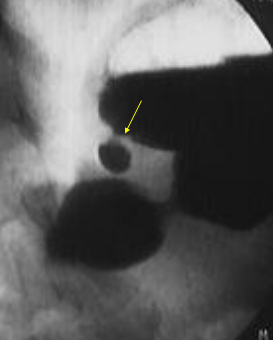

Polip gastric

Diverticul gastric